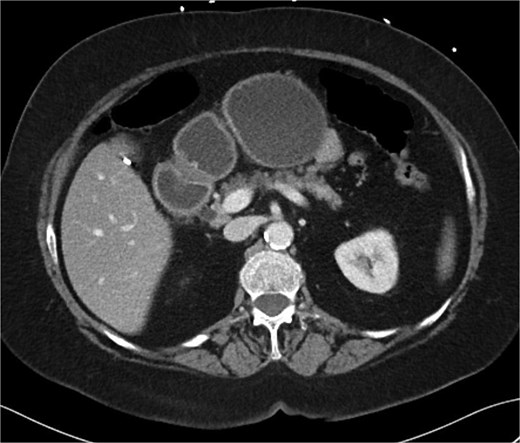

A 70-year-old woman with obesity, non-insulin-dependent diabetes, gastroesophageal reflux disease (GERD), cholecystectomy, and prior RYGB presented to the ED with acute chest and lower abdominal pain. The pain began 1 day earlier and initially responded to Ibuprofen, which she had been taking 4–6 times daily for musculoskeletal discomfort. Her pain worsened, radiating to her back, and was accompanied by belching and vomiting with dry heaving. She denied trauma or changes in bowel habits. Initial CT (Fig. 1) imaging showed a moderate hyperdense area around the duodenum, distension of the afferent limb and excluded stomach, and expected postoperative changes. She was admitted for conservative management. Four days later, a repeat CT (Fig. 2) was performed due to persistent symptoms, revealing free fluid in the intraperitoneal and retroperitoneal spaces, raising concern for duodenal perforation. She developed lethargy and diffuse abdominal tenderness and was taken to the operating room. Exploratory laparotomy with peritoneal washout, enterolysis, partial omentectomy was performed. It revealed two 1 cm posterolateral perforations of D3, which were repaired with an omental pedicle flap. The Roux limb was healthy, the jejunojejunostomy was dilated but patent, and the biliopancreatic limb was intact. Due to high vasopressor requirements, a temporary abdominal closure device was placed, and she was transferred to the surgical ICU. After stabilization, a second-look laparotomy was performed the next day to reinforce the duodenal closure, place a gastrostomy tube for drainage, and insert a J-tube for feeding (Figs 3 and 4). The abdominal wall was closed. On postoperative day 2, a CT with contrast showed extravasation from the duodenal repair site. Interventional radiology placed a transhepatic biliary drain to divert bile and support duodenal patch healing. Helicobacter pylori antigen was negative. Her condition improved, and she was started on an enteral and slow oral feeding regimen. However, at this juncture, the patient declined further treatment and requested comfort care measures.

CT scan A/P of the abdomen and pelvis with IV contrast on presentation showing moderately dilated gastric remnant with thickening of the pylorus and proximal duodenum.